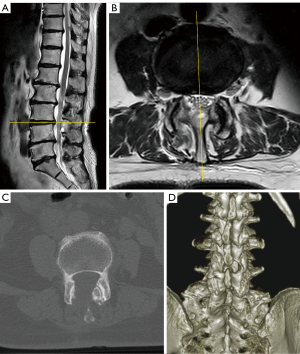

A 70-year-old female with lower back pain and radicular pain in the anterior aspect of her right leg. There was no history of major trauma, lumbar surgery, or antiplatelet/anticoagulant therapy. Muscle strength was not decreased in either leg and tendon reflex findings were unremarkable. Magnetic resonance imaging (MRI) revealed right L4 nerve root compression due to a right LFH and lumbar canal stenosis at L3–4 (Figure 1A-1C). Computed tomography (CT) revealed no calcified lesions within the spinal canal at L3–4 (Figure 1D,1E). Conservative treatment with nonsteroidal anti-inflammatory drugs was initially administered; however, there was insufficient improvement, and a local anesthetic injection into the right L4 nerve root produced a transient improvement in the symptoms. Nevertheless, lower back and radicular pain gradually increased compared to the initial presentation, and the patient underwent FEL under general anesthesia under fluoroscopy.